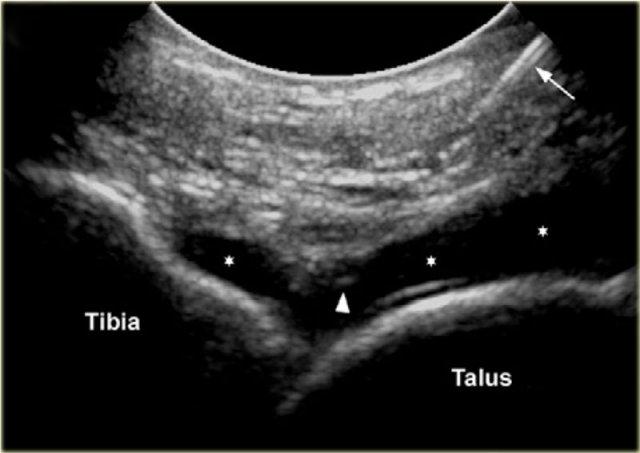

Tibiotalar joint

CT hoặc MR chụp khớp cản quang có thể được sử dụng để đánh giá tổn thương dây chằng, tổn thương xương sụn hoặc sụn khớp, đánh giá các dị vật tự do hoặc đánh giá sự ổn định của các tổn thương xương sụn.

Để tiêm vào khớp cổ chân (khớp chày-sên), bệnh nhân nằm ngửa với bàn chân ở tư thế gấp lòng nhẹ.

Mặt trong của khớp chày-sên được khảo sát ở phía trước bằng siêu âm để xác định vị trí thích hợp cho việc tiêm, đồng thời kiểm tra xem có dịch khớp quá mức hay không.

Chúng tôi sử dụng đầu dò mảng cong nhỏ 8 MHz, nhưng nếu muốn, có thể sử dụng đầu dò mảng tuyến tính 18-12 MHz. Trục dài của đầu dò được giữ trong mặt phẳng đứng dọc.

Sonogram showing the needle (arrow) and the needle tip (arrowhead) and the injected contrast media in the tibiotalar joint.

Kim tiêm, thường là cỡ 22 (dài: 30 mm), được đưa vào dọc theo trục hình ảnh dài của đầu dò ở phía trong của khoang khớp trước, phía trong so với dây chằng chày trước, tránh các dây chằng và mạch máu.

Cần xác định vòm xương sên và bờ trước xương chày nhô ra. Kim được đưa vào khớp theo hướng từ đuôi lên đầu, dưới bờ bụng của đầu xa xương chày, hướng vào bề mặt khớp của đầu xa xương chày.

Cảm nhận được sự tiếp xúc và một lần nữa đảm bảo rằng đầu kim không chạm vào sụn xương chày và mặt vát của kim hướng vào trong khớp.

8-10 ml thuốc cản quang được tiêm vào khớp chày-sên và người ta thấy bao khớp phía trước phồng lên do dịch.

Không nên có sức cản khi tiêm hoặc đau mà bệnh nhân cảm thấy.